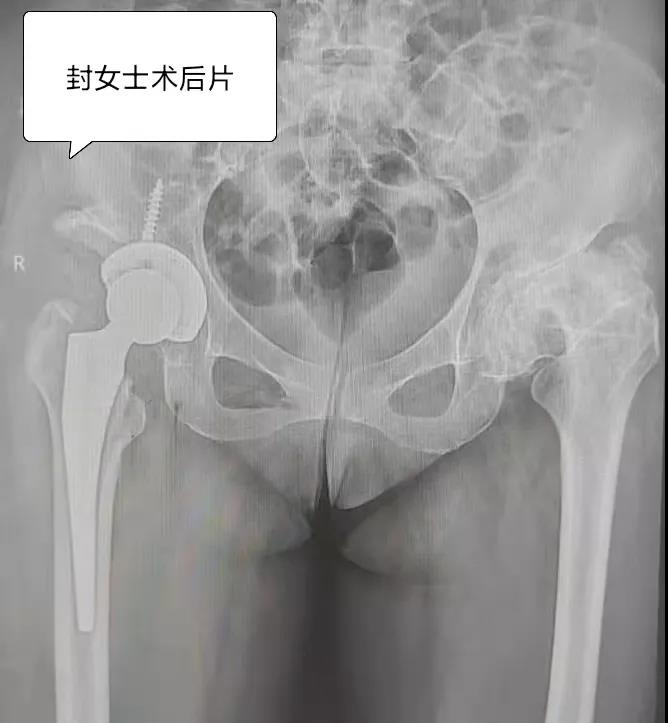

2021年11月16日,来自玉林容县的廖女士和封女士相约到我院髋关节一科住院治疗,她们既是同乡,也是相识多年的好友,而她们现在亦是“同病相怜”的病友。廖女士今年61岁,因双髋部及左大腿疼痛2年余,反复在多家医院和私人诊所进行诊治,但疼痛仍不能减轻,并有加重的现象,只能扶拐行走,长期依赖止痛药,给生活带来了诸多不便。 ※廖女士术前骨盆平片

廖女士经多方打听,知悉玉林市中西医结合骨科医院对此类疾病治疗效果很好,约封女士回来,找到髋关节一科黎观保主任一同进行诊治。经过黎观保主任仔细体格检查,结合影像学等相关资料,对廖女士和封女士的病情进行综合分析,廖女士双侧股骨头缺血性坏死,负重区塌陷,FicatⅣ期。封女士双侧髋关节发育不良并骨性关节病,关节间隙明显变窄,骨赘增生明显,关节屈伸旋转活动严重受限。两位病友双髋部疼痛,功能受限严重影响了她们的生活质量。根据她们的病情,黎观保主任与她们进行了详细的病情沟通,她们也选择了先行一侧髋关节置换手术的方案。于2021年11月22日,在麻醉科的积极配合下,黎观保主任为廖女士行“左侧人工全髋关节术”,为封女士行“右侧的人工全髋关节置换手术”,术中均采取DAA入路,应用Anterior Path微创关节置换技术。此技术创伤轻、出血少,人工关节安装精确,术后疼痛轻。黎观保主任鼓励她们术后从手术室走出来,“这可能吗?”廖女士、封女士满脸充满了疑虑,听说以前做手术还要在床上躺半个多月呢。经过黎主任的鼓励,加上术后自身的良好状态,从小心翼翼的试探到慢慢的从容下地,患者从手术室走出来了。